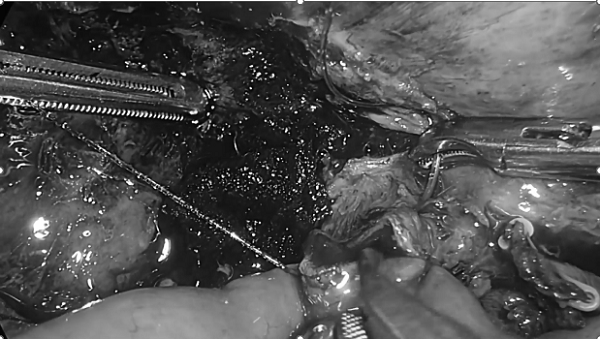

3.胆肠吻合

4.肠肠吻合